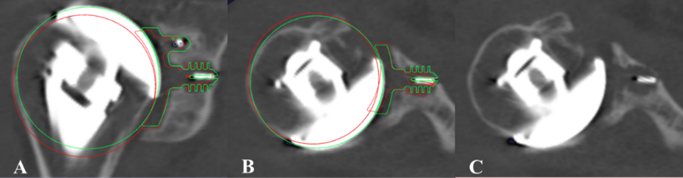

Imaging Arthroplasty

PI: Eric Ricchetti, MD

Co-Is: Joseph Iannotti, Carlos Higuera, Wael Barsoum, Peter Evans, Luke Nystrom, George Muschler, Richard Parker, William Seitz, Jonathan Schaffer, Nicolas Piuzzi, Bong-Jae Jun, Ahmet Erdemir, Thomas Daly, Xiaochun (Susan) Zhang, Naveen Subhas, Jarrod Dalton, Vahid Entezari

Abstract:

The Arthroplasty Research program focuses on identifying the demographic, disease-related, and surgical factors associated with short- and longer-term clinical outcomes following joint arthroplasty of the hip, knee, and shoulder, including potentially modifiable factors.Our aim is to improve clinical decision-making, patient selection, clinical outcomes and implant survivorship in total joint arthroplasty through the modification of key demographic, disease-related, and surgical factors,either pre-operatively or through surgical treatment. We have developed and utilize unique research tools to achieve this aim, including synovial fluid biomarker analysis in the setting of periprosthetic joint infection and post-operative three-dimensional CT imaging analysis of implant position over time. Our research program involves collaboration of faculty across orthopaedic surgery, biomedical engineering, radiology, pathology, and biostatistics.